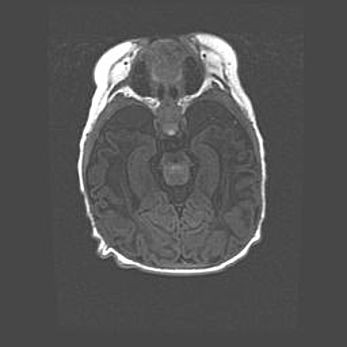

Открытая гидроцефалия.

Возраст: 9 месяцев 12 дней

Вес: 6800 г

Пол: мужской

Окружность головы: 41,5 см

Срок гестации: 28 недель

Гидроцефалия головного мозга у новорожденных имеет характерный признак: опережающий рост окружности головы приводит к визуально хорошо определяемой гидроцефальной форме сильно увеличенного в объёме черепа. Детские неврологи определяют следующие симптомы гидроцефалии у грудничков: выбухающий напряжённый родничок, частое запрокидывание головы, смещение глазных яблок к низу.